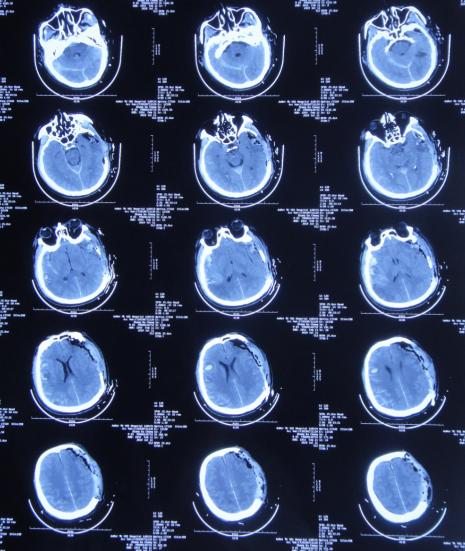

左颞叶血肿清除+去骨瓣减压术后第45天,即2019年8月24日,复查头颅CT( 图-3 )示颅脑术后改变,脑室基本“正常”,脑室周围稍水肿。

图-3: 2019年8月24日头颅CT

左颞叶血肿清除+去骨瓣减压术后第52天,即2019年8月31日,复查头颅CT( 图-4 )示脑室较前无明显变化,脑室周围仍稍水肿。

图-4: 2019年8月31日头颅CT

左颞叶血肿清除+去骨瓣减压术后第63天,即2019年9月11日患者言语较前清晰,单侧搀扶下可行走,复查头颅CT( 图-5 )(双颞增大)脑室较前仍无明显变化,但脑室周围水肿稍加重。

图-5: 2019年9月11日头颅CT

左颞叶血肿清除+去骨瓣减压术后第99天,即2019年10月17日患者言语基本清晰,可独立缓慢行走,复查头颅CT( 图-6 )示:颅脑术后改变,脑室较前无变化,脑室周围水肿较前无变化。

图-6: 2019年10月17日头颅CT